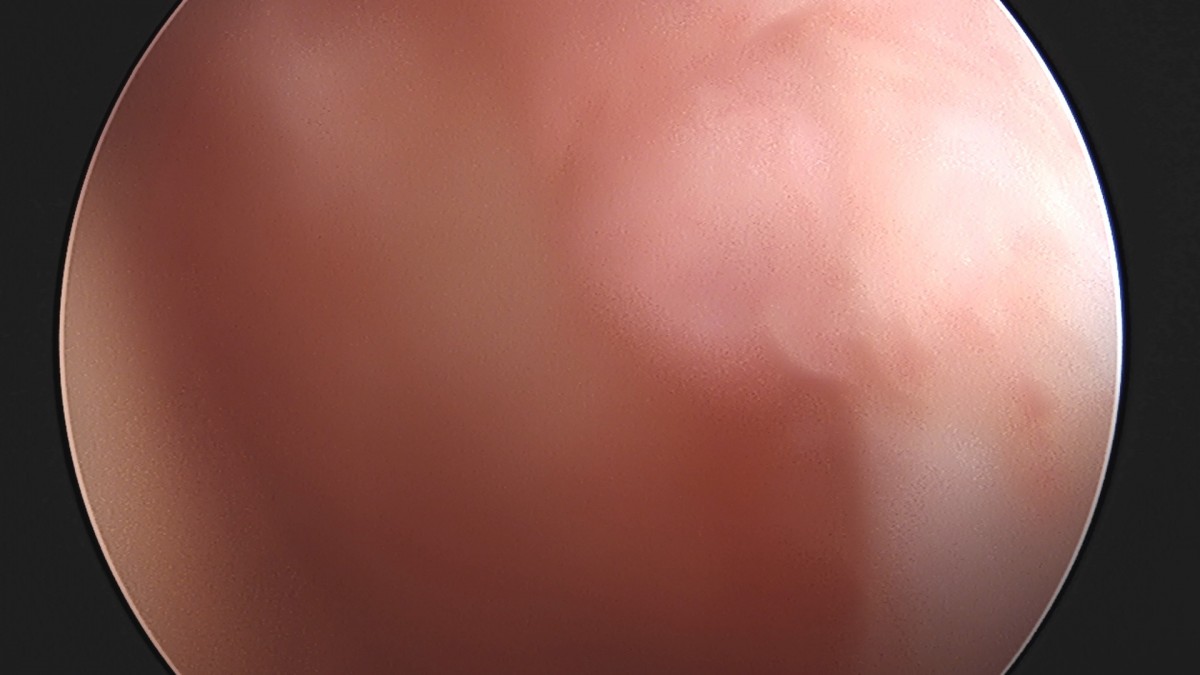

정지영원장님 어깨 관절낭 이완술 및 석회제거술 박설O 환자

작성자 최고관리자 댓글 0건 조회 732회 작성일 25-09-16 16:59